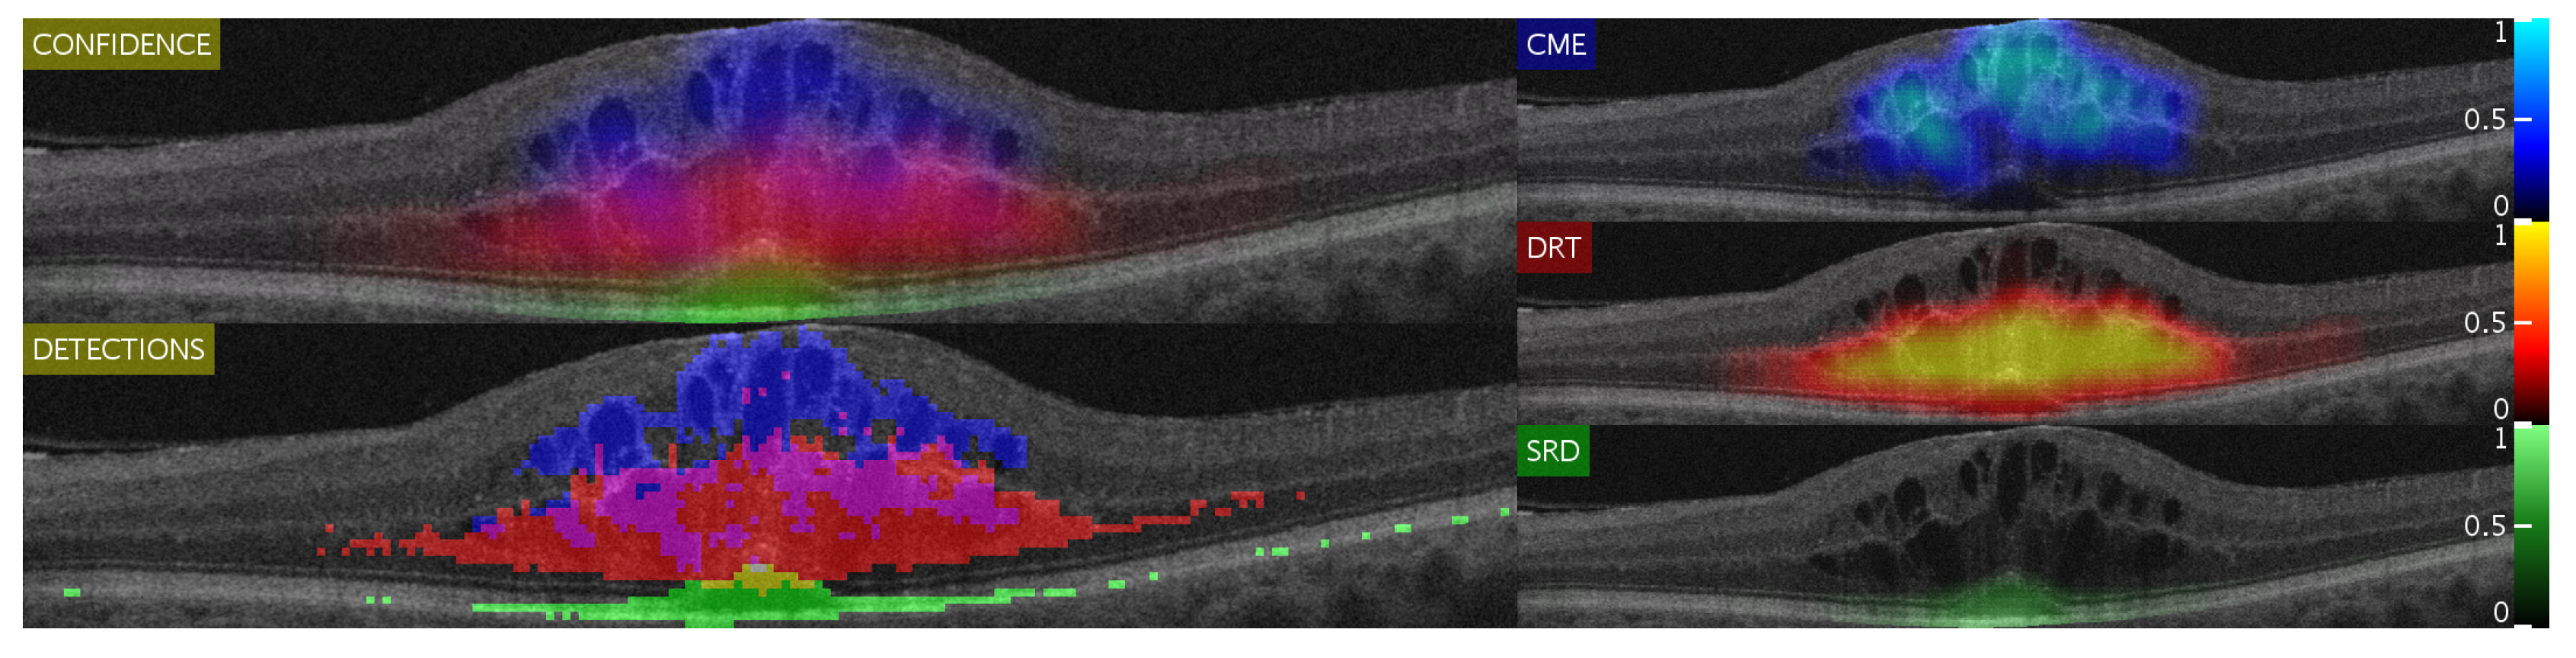

By doing so, we can obtain a matrix composed by three feature vectors (one for each type of DME and optimal features defined by the SFS algorithm for each class). These classifications are used by two different complementary algorithms, the Confidence map and the Binary map. Finally, when the two types of maps are generated, its information is used to generate an intuitive visualization of the detection and characterization of the different ME types to facilitate their inspection by the specialists. This visualization consists in a 5-window representation of different points of view of the detections with two main representations:

- The “CONFIDENCE” window shows a merged representation of all the pathology confidences and the interactions between them. This window allows experts to study the possible overlap between the types of pathology that cannot be achieved through segmentation. In addition, it clearly presents the interactions that cannot be observed in the windows of the other types on their own. With this same idea (displaying the confidence on the detections), the 3 right-sided windows show, independently, each of the confidences given by the confidence map algorithm, but using a color map with a higher degree of granularity (so an expert clinician can see the nuances between in the confidence levels).

- The “DETECTIONS” window represents all the detections, without displaying the confidence the system infers in them. This allows the experts to have a different perspective of the detections, showing a more explicit representation of the independent regions that have tested as positive (as well as an interpolation of the surrounding regions that may also be candidates). In doing so, it complements the information shown in the “CONFIDENCE” window.

An example of the results that can be generated by this strategy is represented in Figure 6. As can be seen in this image, despite the binary map showing a set of false positives, the confidence maps actually highlight the correct regions as important. The same way, specially in the case of DRT, it is interesting to also analyze any detection, as even expert clinicians have issues detecting where or where not the diffuse limits of the DRT end.

Figure 6.

Example of a generated image showing all five different points of view. As shown, leftmost representations give a general idea of the interaction between DME types. On the other hand, the rightmost maps present a more detailed characterization.

Figure 14 and Figure 15 show representative examples from the test set with a healthy image and another one with different types of pathological fluid generated with the Spectralis and Cirrus devices, respectively. In addition, the labels of the expert are included to compare with the results. As can be seen, in both cases, the system is capable of satisfactorily detecting the pathological fluid accumulations whenever they are present, although we can see spurious detections in the cases of both Figure 14a and Figure 15a. However, these detections can be easily corrected with post-processing strategies as mentioned before, but we decided to include them for a better understanding of the behavior of the system.

In these visualizations, we can observe two major phenomena. The first one consists in the tendency to spurious detections in the images generated by the Spectralis of the SRD-type edema. This may be due to the higher contrast of the images generated by this device, favouring the appearance of common patterns of the SRD-type edema not present in the images that are generated with Cirrus. On the other hand, we can see a clear tendency in the Cirrus images to generate small detections of DRT-type edema. This is due to what was already mentioned in the section where we analyzed the selection of features: the DRT pattern of the images that are generated with the Cirrus device is very similar to the normal tissue in comparison with the "wet" and coarse texture of the DRT fluid accumulations in images that are generated with the Spectralis device.